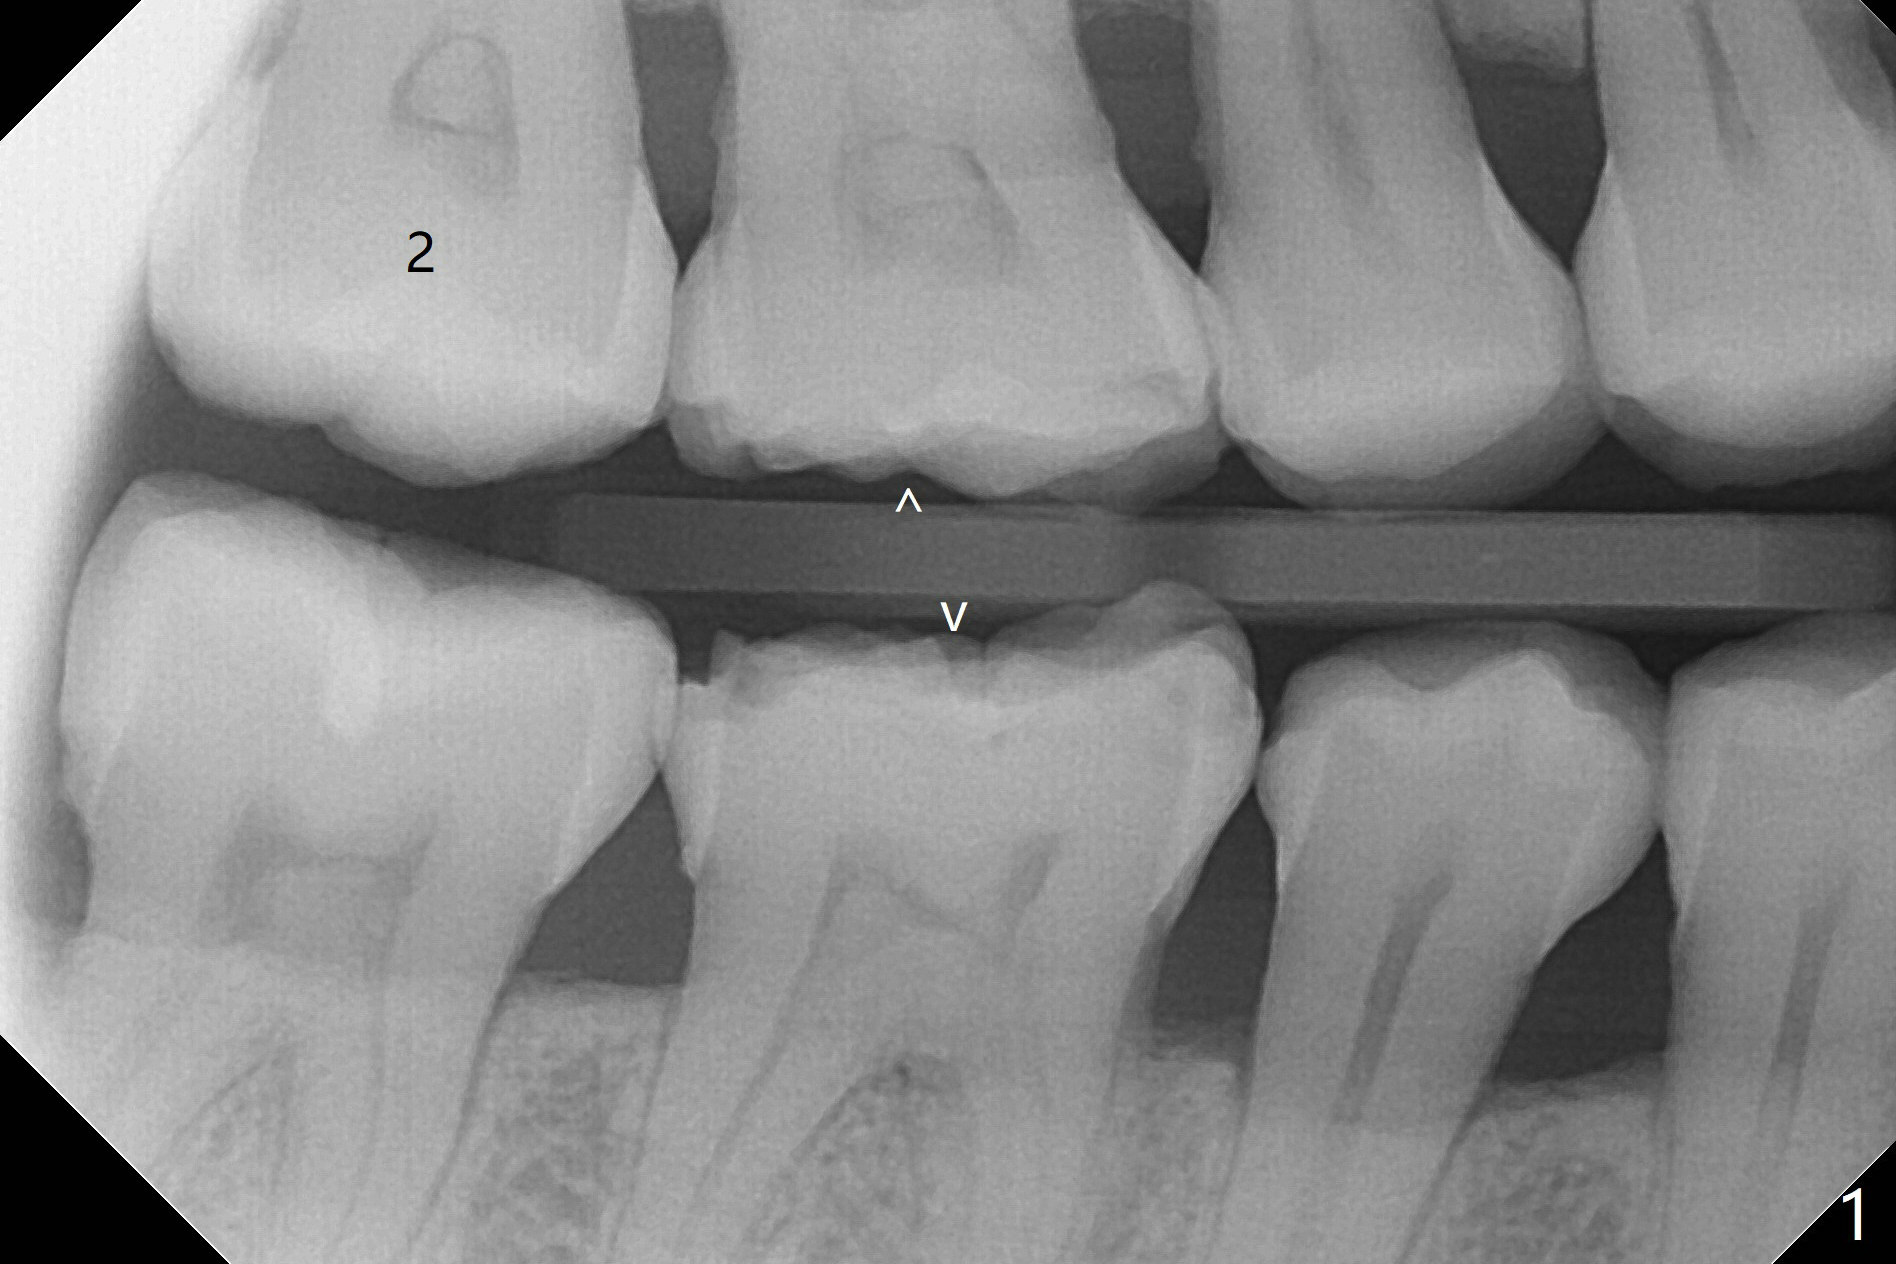

A 52-year-old woman had palatal periodontal infection at #2 a half month earlier (Fig.1,2), which was treated with Arestin. When she returns, the tooth #4 has palatal subgingival oblique fracture (Fig.3 <), interfering with mastication. Due to emergency, free hand immediate implant is planned. The buccal apical defect (Fig.3 *) will be repaired with PRF membrane (x1) and allograft after osteotomy (with gauze in place). A 4.5x20 mm tissue-level implant will be placed (Fig.4) instead of a bone-level one (Fig.5).